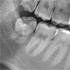

Nacholgend ein paar phänomenale Bilder & Werte,

die nicht nur einem Fachmann die Sprache verschlagen:

Aufnahmeparameter: Ceph LA; 82 kV; 10 mA; 8.0 s; 0.8 mm CU + 6.0 mm AL

gemessene Dosis: 2.99 µGy